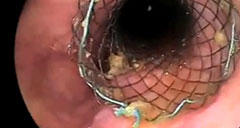

Animación del stent biliar metálico WallFlex® con imágenes clínicas

Animación del stent metálico totalmente cubierto WallFlex®. Esta animación incluye imágenes clínicas y demuestra las características de este stent, así como el procedimiento de despliegue.